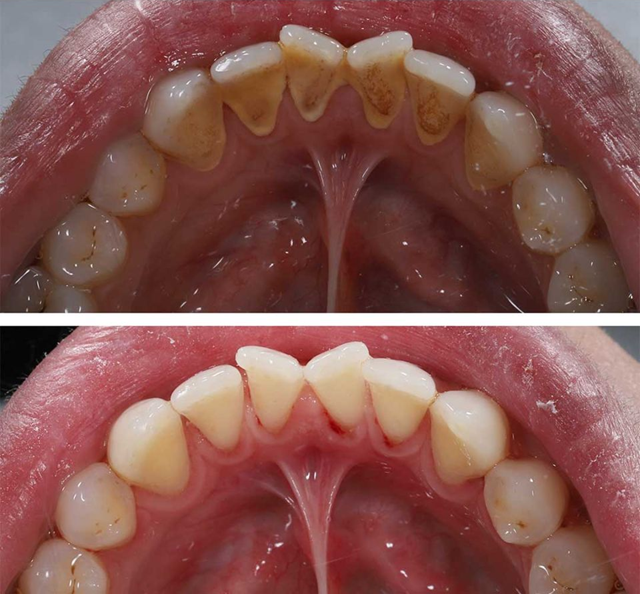

Oto 7 najlepszych sposobów, które pomogą Ci pozbyć się plam kamienia nazębnego przy minimalnym wysiłku, przy użyciu prostych składników lub nawyków. Te metody nie…